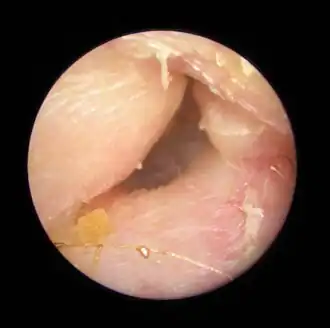

Exostoses dans le conduit auditif, vues par otoscopie.